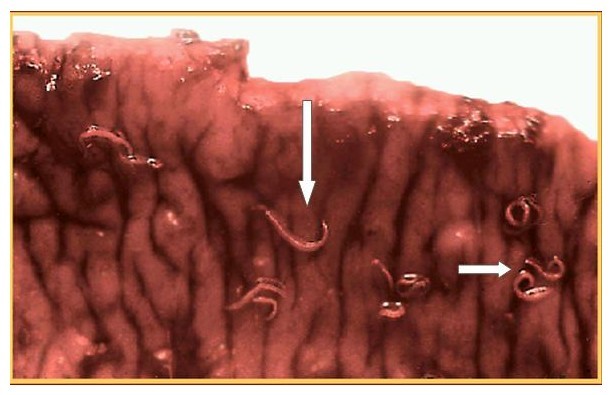

钩虫的成虫喜欢寄生在肠道内,口囊咬住肠粘膜,会造成肠内出血和溃疡。重者甚至被钩虫侵害至粘膜下层甚至肌层。

钩虫本来在宿主体内就是以吸血为生,不仅如此,钩虫咬附部位还会往外渗透血液,且钩虫不断变换咬附位置。